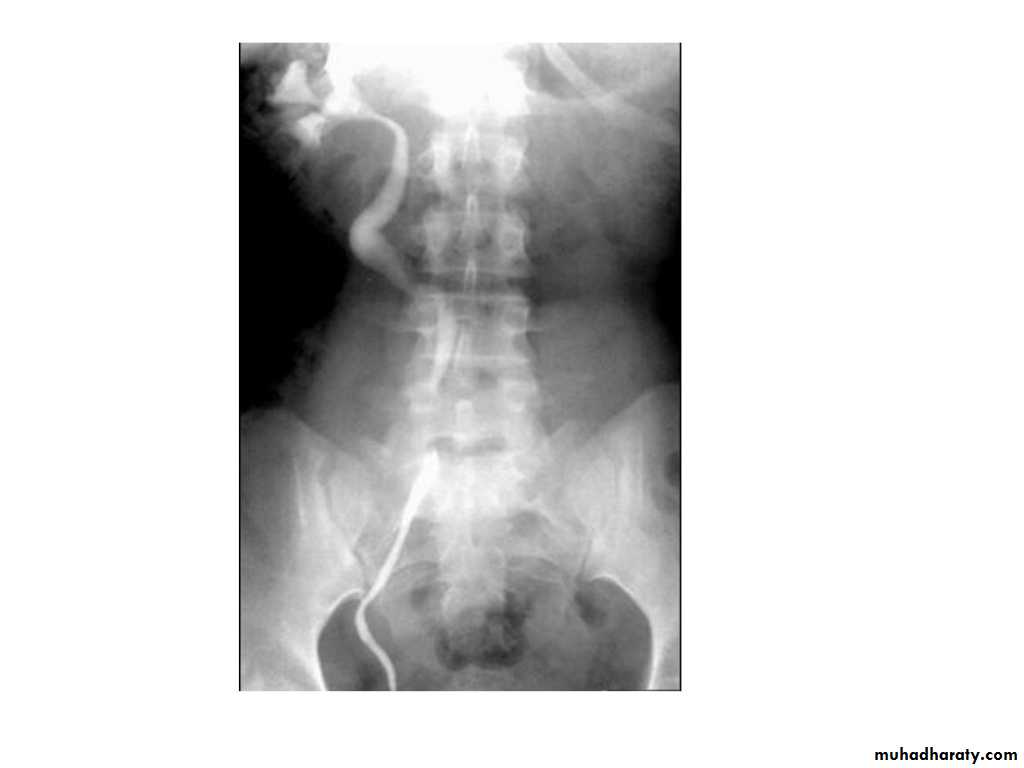

IVU shows

1. The kidneys at low position .2.Close to the spine with long axis parallel to the spine

3. Malrotation manifested by medially directed calyces.

4- The renal pelvis and ureters are anterior and lateral in position.

5- Hydronephrosis and calculi highly associated.